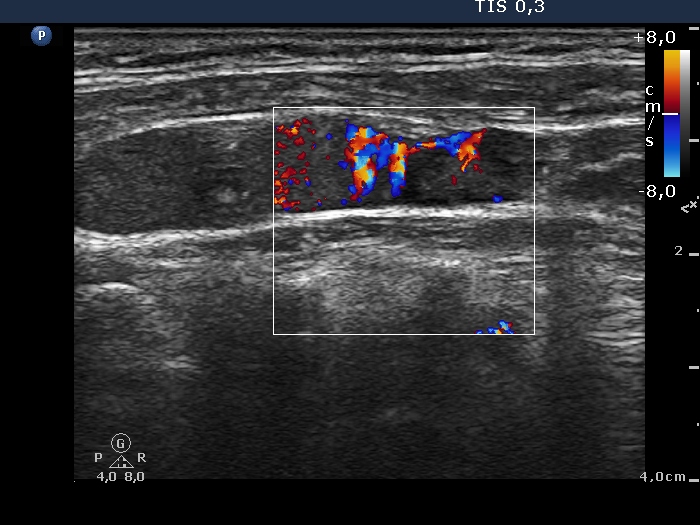

Follow-up examination 17 months after first visit (second and third rows):

Ultrasonography: The echogenicity index of the thyroid was 50%. The vascularization was not significantly increased. There was a large hypoechogenic, inhomogeneous nodule in the upper part of the left lobe. Both the intranodular and the perinodular blood flows were increased.

1. It seems to be a reasonable assumption that papillary cancer had been already present at the first investigation. It was very unusual that the left thyroid was significantly more inhomogeneous than the right lobe. The former contained relatively large hyperechogenic granules, however, there were no discrete circumscribed lesion in the left lobe.

2. It is worth analyzing the video recorded at the second examination. Both the nodule and the extranodular part present fibrotic changes, moreover the inhomogeneity of the extranodular part is more pronounced than that of the nodule.